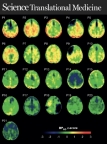

Invicro scientists published in Science Translational Medicine (Graphic: Business Wire)

Invicro London scientists, Doctors Alex Whittington, Jan Passchier and Roger Gunn, are co-authors of this revolutionary study that uses positron emission tomography (PET) to understand tau pathology in traumatic brain injuries (TBI), years after they occur. The results illustrate that tau PET is an encouraging approach for measurement of progressive neurodegeneration associated with tauopathy following TBI.

TBI can lead to life-long chronic neurodegeneration, including the possibility of dementia. The publication examines how the use of Flortaucipir ([18F]AV-1451, [18F]T807), a PET radioligand for tau, enables the examination of tau pathology in vivo in subjects who are long-term survivors of brain injuries. Flortaucipir has demonstrated potent and specific non-displaceable binding to tau neurofibrillary tangles in both post-mortem human brain tissue and brain scans of subjects with Alzheimer Disease. This study elegantly shows how tau signals can now also be detected in subjects suffering from brain injuries.